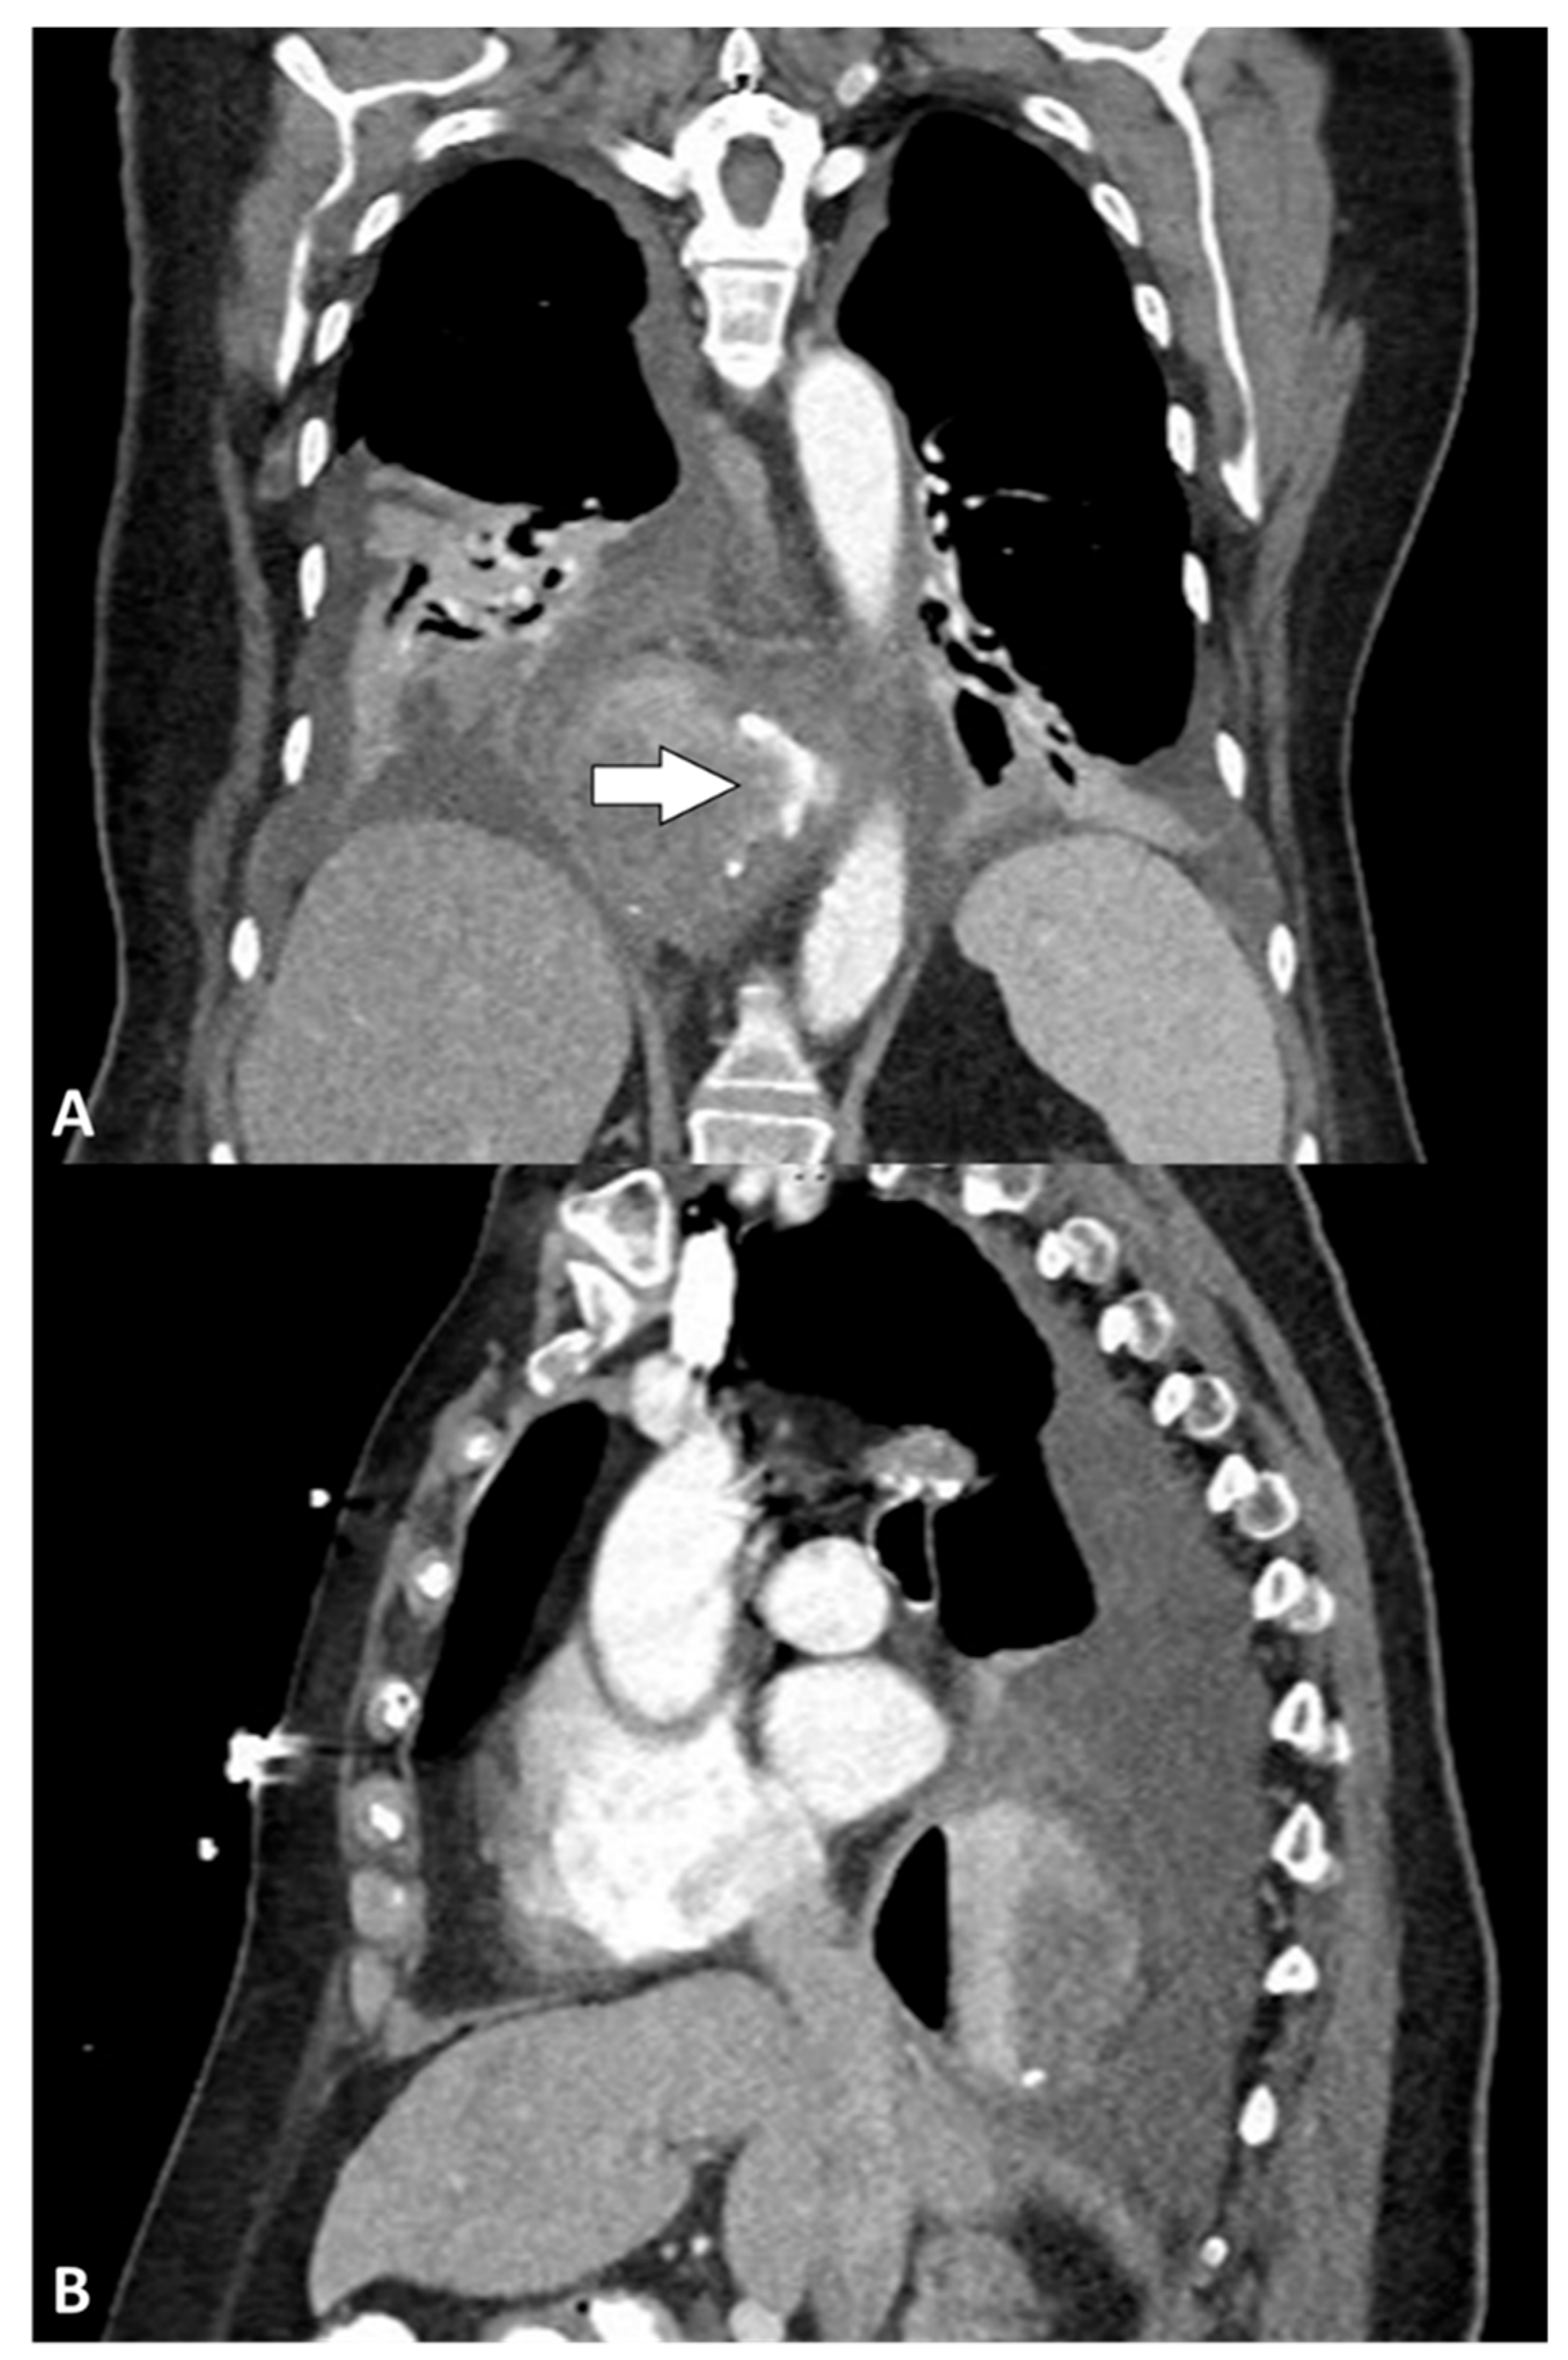

The median time between LARS and clinical presentation with leak was 2 (IQR: 1–8) days, ranging from 1 to 15 days. The most frequent symptoms were shortness of breath (all patients) and pain (three [60%] patients). The pain manifested in various forms, including diffuse abdominal pain, thoracic and midscapular pain, and stabbing thoracic pain. All patients presented with hypoxia (i.e., resting SaO2 of less than or equal to 95%) [13], and four (80%) required emergent intubation. Septic shock, according to the Sepsis-3 definitions [14], was reported at presentation in four (80%) patients. New-onset atrial fibrillation was observed in one (20%) patient, three (60%) patients had a clinical or radiological diagnosis of subcutaneous emphysema, and three (60%) patients had acute kidney injury at presentation. Notably, fever (i.e., body temperature > 37.5 °C) was absent in all patients. The median white blood cell count was 14.5 × 109/L (IQR, 13.8–16.5), and the rest of the bloodwork was unremarkable. The first diagnostic hypotheses were postoperative leak in two (40%) patients, pneumonia in two (40%) patients, and non-ST-elevation myocardial infarction (NSTEMI) in one (20%) patient. The first imaging test for all patients was a chest X-ray, and three (60%) patients underwent multiple chest X-rays before progressing to second-level imaging modalities. Three (60%) patients underwent an esophagram study, although only one (33.3%) was conclusive for an esophageal leak, whereas two (66.7%) were considered negative. All patients underwent computed tomography (CT), which provided a definitive diagnosis in all cases. Four (80%) CT scans were performed with oral contrast, all of which revealed extraluminal extravasation. Three (60%) patients had a pneumothorax, one of whom presented with tension pneumothorax. Figure 1 shows a CT scan performed for a perforation diagnosis. Two (40%) patients showed a radiological recurrence of hiatal hernia. Before consultation by our department, two (40%) patients had undergone chest tube placement immediately after receiving a diagnosis of esophageal perforation (one of them drained brown fluid and one drained purulent fluid), and one (20%) patient underwent endoscopic placement of a covered esophageal stent. The clinical presentations and imaging characteristics are summarized in Table 2.

Figure 1.

Computed tomography: (A) coronal and (B) sagittal views showing air and fluid collection surrounding the distal esophagus with oral contrast extravasation (arrow).